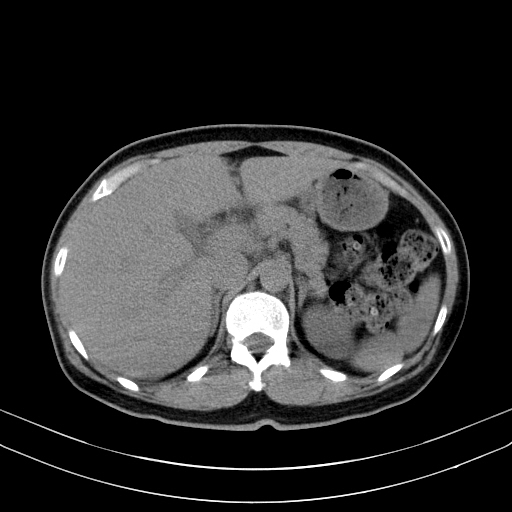

상복부통증을 주소로 내원한 50세 남자환자의 복부CT영상입니다. 담낭벽이 두꺼워져 있어 담낭염이 의심되어 치료하였으며, 조영증강 전 및 조영증강 후 영상에서 간 내에 별다른 국소병변은 보이지 않습니다.